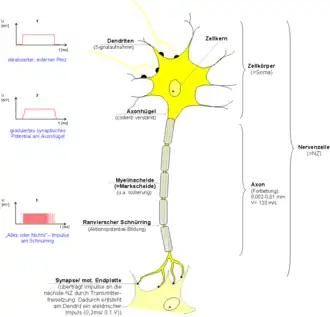

Myelinisierung wird die mehrfache Umwicklung des Neuriten einer Nervenzelle durch umhüllende Gliazellen genannt, wodurch das Axon elektrisch derart isoliert wird, dass mit Umbau seiner Internodien eine schnellere Erregungsleitung möglich wird. Fortsätze von Nervenzellen werden zunächst einfach von Gliazellen umhüllt, und erst später manche mehrfach und so zu myelinisierten (markhaltigen) Nervenfasern. Dieser Vorgang läuft ontogenetisch mit einer bestimmten Reihenfolge ab, in der sich oft auch eine Abfolge von Schritten der Entwicklungsgeschichte des Nervensystems und des Gehirns widerspiegelt – worauf bereits Paul Flechsig (1847–1929) hinwies.[1] So werden beispielsweise motorische vor sensiblen myelinisiert, und grundlegende Verknüpfungen vor zusätzlichen. Denn manche Verbindungen können erst dann funktional werden, wenn andere dies schon sind.

Aussprossende Nervenzellfortsätze werden von Gliazellen umgeben, beständige erhalten eine gliäre Umhüllung, viele dann später während bestimmter Phasen der Entwicklung auch eine regelrechte Myelinscheide oder Markscheide. Innerhalb des ZNS wird sie von Oligodendrogliazellen gebildet, die aus Neuroepithelzellen des Neuralrohrs hervorgehen. Außerhalb, bei den Nervenfasern des peripheren Nervensystems wird diese Aufgabe von Schwann-Zellen übernommen, Gliazellen, die aus neuroektodermalen Zellen der Neuralleisten hervorgehen.

Die Schwann-Zellen wachsen während der Entwicklung der Myelinscheiden (Myelogenese oder Markreifung) je nach Typ der Nervenzelle bis etwa 50-mal um deren Nervenzellfortsatz herum und wickeln ihn dabei mit Doppellagen ihrer Zellmembran mehrfach ein. Eine einzelne Schwann-Zelle umwickelt dabei immer nur einen bis 2 mm langen Teilabschnitt eines Axons, das Internodium, viele Schwann-Zellen liegen daher nebeneinander aufgereiht längs dem gemeinsamen Achsenzylinder um das Axon herum.[3]

Mit zunehmender Anzahl der Wicklungen nimmt der Durchmesser einer Nervenfaser bei gleichem Axondurchmesser zu. Je nach Dicke der Myelinscheide bzw. Anzahl der Markscheidenlamellen unterscheidet man die markhaltigen Nervenfasern in markreiche (stark myelinisierte) und markarme Nervenfasern. Sogenannte marklose Nervenfasern (besser: markscheidenlose, auch Remak-Fasern, nach Robert Remak) haben keine Markscheide, doch im PNS ebenfalls eine Umhüllung durch Gliazellen, in deren Seitenfalten sie verlaufen. Diese einschichtige Hülle isoliert allerdings so wenig, dass Aktionspotentiale kontinuierlich weitergeleitet werden müssen, weshalb die Erregungsleitung deutlich langsamer ist als bei Axonen in einer Myelinscheide.

Bei somatischen Nervenfasern, die afferent oder efferent die Leibeswand beziehen – und so rasche Reaktionen auf Veränderungen der Umgebung vermitteln können – stellen die markhaltigen Nervenfasern den größten Anteil. Deren Axondurchmesser macht nur noch etwa die Hälfte des Nervenfaserquerschnitts aus, wegen der dicken Isolierungsschicht. Diese erst ermöglicht die sogenannte saltatorische Erregungsleitung mit einer mehrfach erhöhten Nervenleitgeschwindigkeit. Hierfür bleibt zwischen zwei Schwann-Zellen eine kleine Lücke, Ranvierscher Schnürring oder Knoten (lateinisch nodus) genannt, und nur noch in diesem (nodalen) Bereich liegt das Axon so frei, dass hier ein Aktionspotential aufgebaut werden kann – was je eine gewisse Zeit beansprucht. Dagegen wird die stark isolierte (internodale) Spanne zwischen zwei Schnürringen nun allein durch schnelle elektrotonische Fortleitung überbrückt, sodass die Aktionspotentiale nur mehr sprunghaft auftretend weitergeleitet werden. Bei demyelinisierenden Erkrankungen, beispielsweise einer Multiplen Sklerose, geht abschnittsweise die Myelinscheide um Axone von zentralen Neuronen verloren, wodurch diese Erregungsleitung gestört wird, was sich unter anderem in Gefühlsstörungen oder Lähmungen äußern kann.